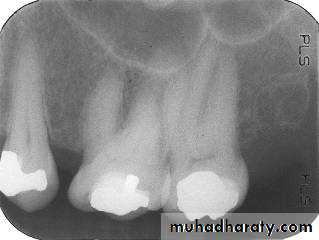

The molar-bitewing. A, Film placement. B, Resultant radiograph.

A

B